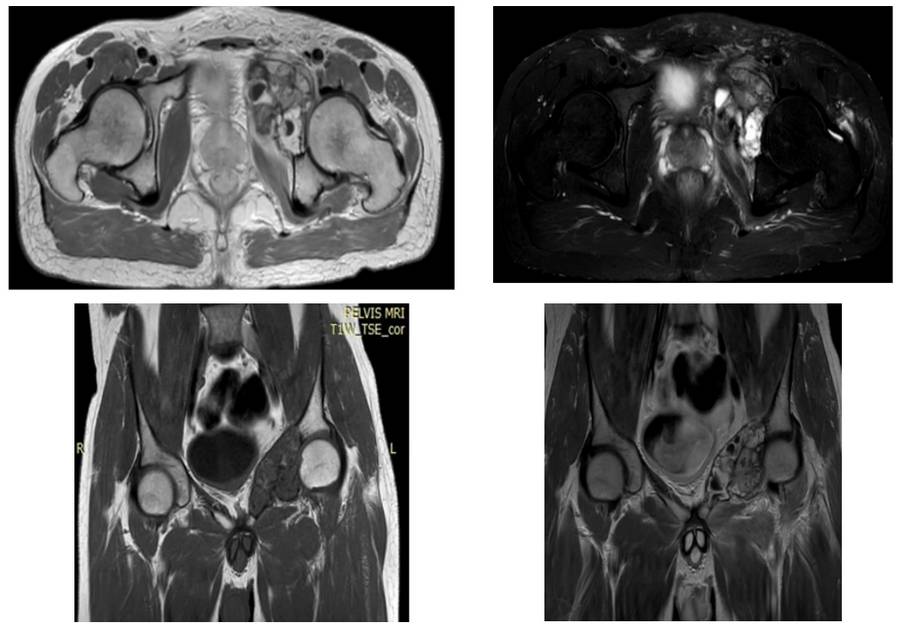

Preoperative: MRI shows irregularly bordered tumor tissue extending into soft tissue and causing bone destruction in the left acetabulum and pubic arm.

Preoperative: MRI shows tumor tissue extending into the soft tissue of the right acetabulum and pubic arm, causing bone damage.